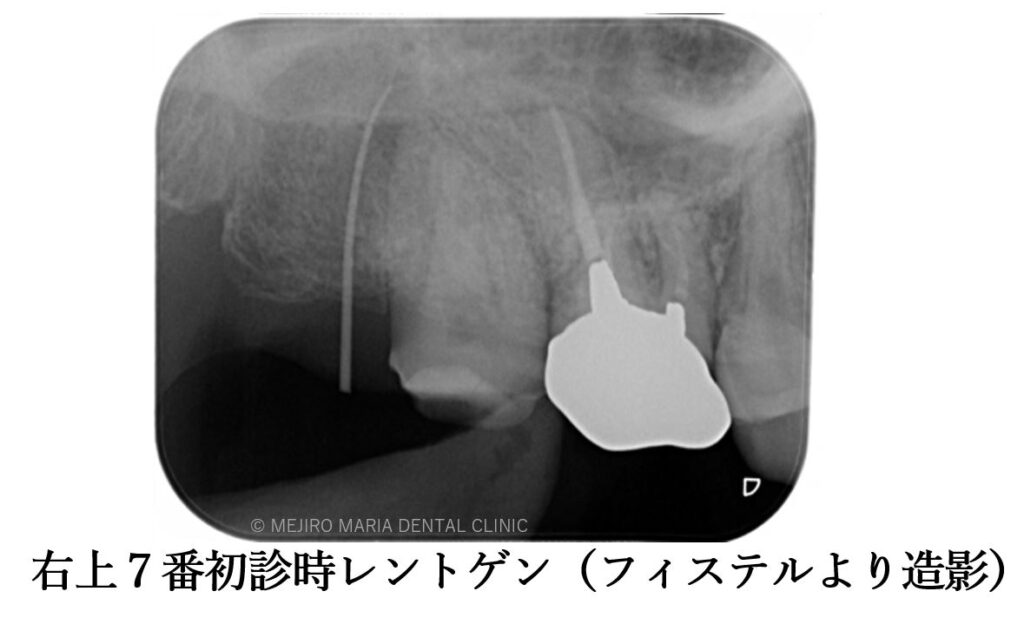

目白マリア歯科 親知らずの移植でインプラントを回避した症例初診時レントゲン画像フィステルより造影

数年前より右上に咬合時の痛み(鋭く刺すような痛み)を感じるようになり、数件の歯科医院を受診するも原因の特定には至らず、経過を見るようにと言われていたとのことです。最後に通院した歯科医院にてクラックが発見されましたが、痛みは良くならず当院を受診されました。

初診時には右上7番に歯髄生活反応は確認できず、歯髄壊死が起因の根尖性歯周炎と診断しました。根管治療を開始するも、歯牙は既に破折しており患者様には抜歯することをおすすめさせていただきました。

クラックトゥースシンドローム(歯に微小な亀裂が入ることで、かみ合わせ時に痛みを感じる症状)は、正確な診査を行わないと原因歯の特定は困難なため、一般歯科医院では原因不明と言われ見逃されやすい歯のトラブルです。

クラックトゥースの診断が遅れることで、今回のように垂直性の破折を起こしてしまう可能性が高まります。